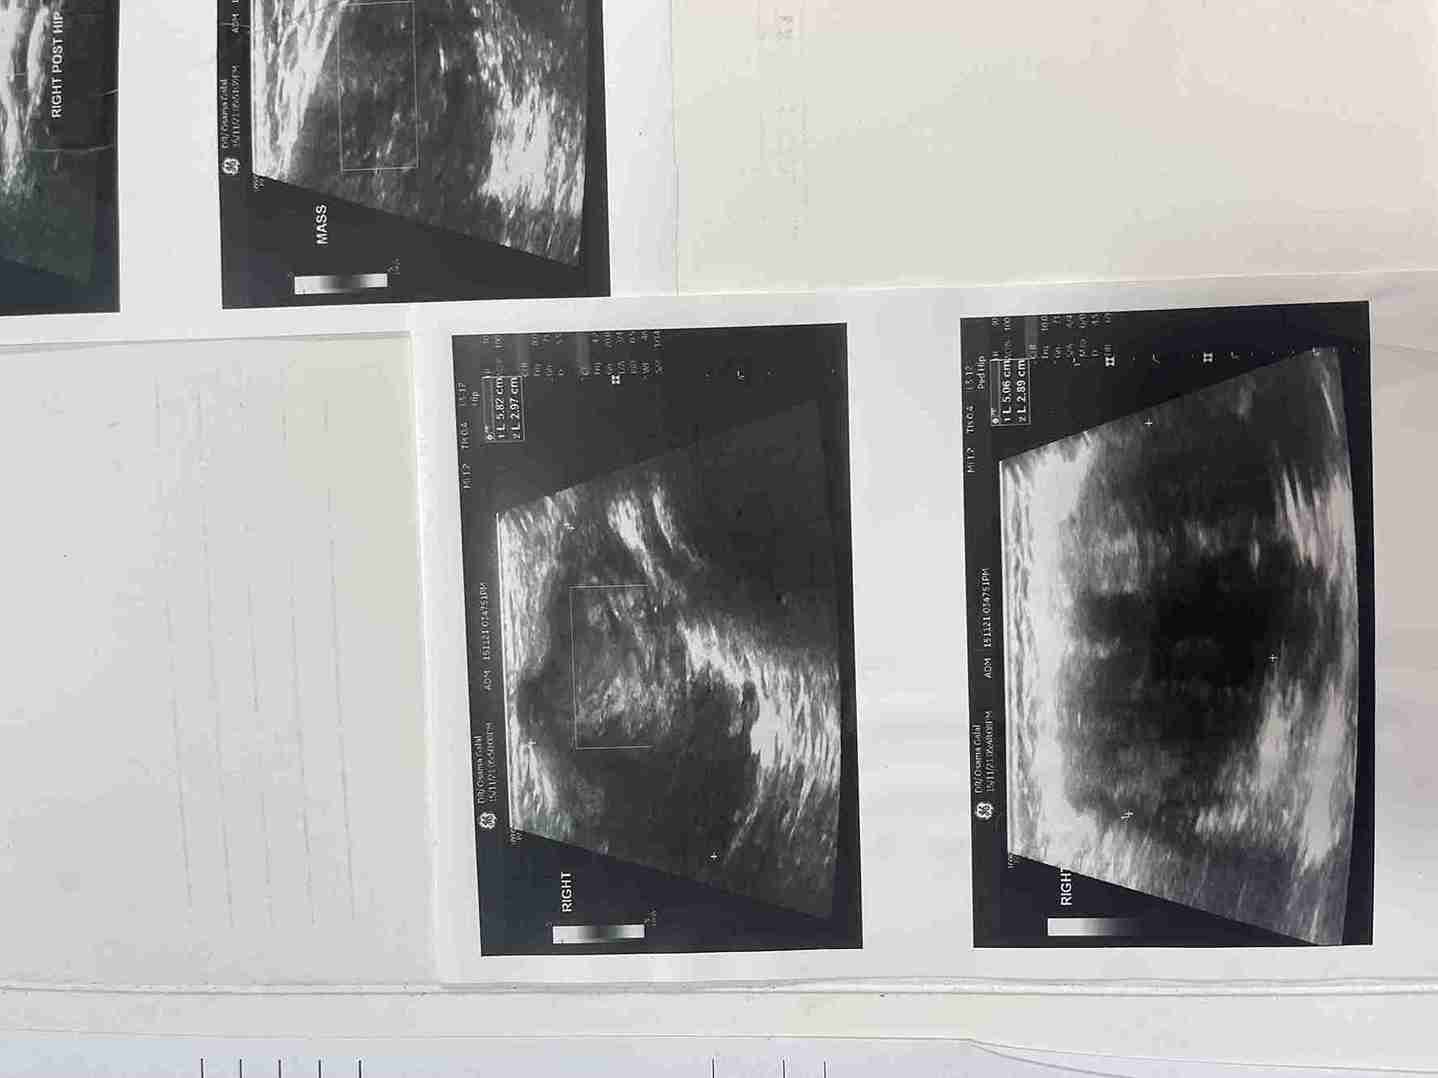

تم في هذه الحالة استئصال ورم حميد نادر (شوانوما) كان موجوداً على غلاف العصب الوركي (عرق النسا) الأيمن لطفلة تبلغ من العمر 5 سنوات ونصف. الورم كان يضغط على العصب مسبباً ألماً في منطقة الفخذ والأرداف. تمت الجراحة بنجاح تام مع الحفاظ الكامل على سلامة ووظيفة العصب.

• وجود كتلة محسوسة يمكن اكتشافها بالفحص.

• نتائج التحليل النسيجي أكدت أن الورم حميد (شوانوما).